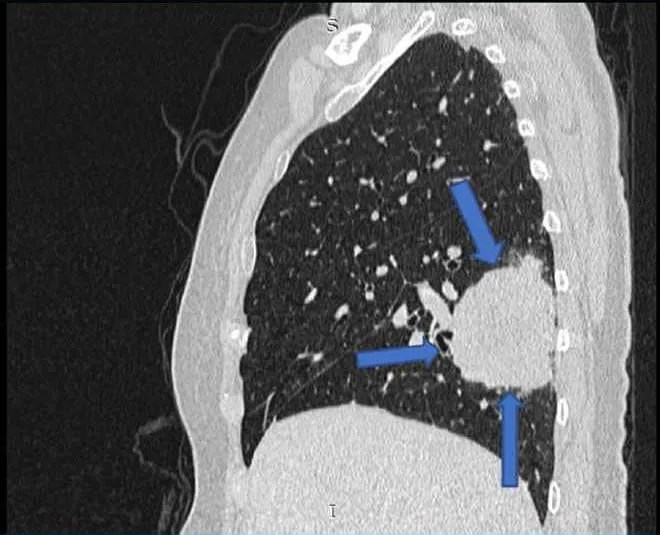

在关节炎出现六个月后,她因腹痛主诉到一家私人医院就诊,接受含网膜活检的小型开腹手术。网膜病理学检查发现II级卵巢浆液性囊腺癌的转移灶沉积。她被诊断为IIIc期卵巢癌,开始新辅助化疗,方案为卡铂(AUC=5,d1)+紫杉醇(80 mg/m2,d1,d8,d15),每21天一周期,共6个周期。SSZ停药。经过三个周期的化疗后,患者出现了新的呼吸道症状。胸部/腹部重复CT显示左侧肺尖后部肿块,双侧肺多发结节,子宫底区域有边界不清的低密度肿块(图3、4)。随后进行了硬质支气管镜检查,发现左上肺叶有一个带蒂肿瘤,几乎完全闭塞了远端左主支气管。肿瘤活检显示为具有肉瘤样特征的恶性肿瘤。

图2. 胸部计算机断层扫描显示右下叶肿块,周围有卫星结节(箭头)